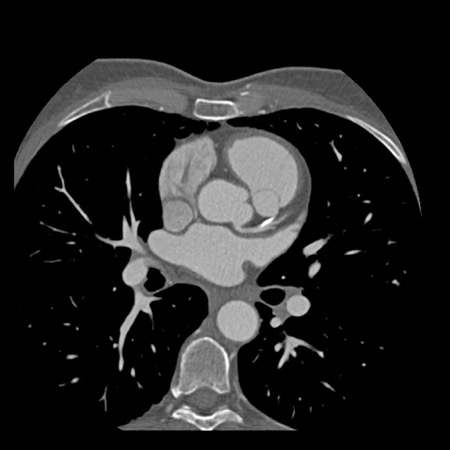

case 1 – CAD-RADS 2/P1

First, scroll through the scan.

Not all images are included. Some images without any abnormalities are skipped

from the series.

How would you describe the findings on the coronary CTA?

The findings are:

- Agatston score of

this patient was 14 (P1). Please, also note the calcification of the aortic valve. - Some partially

calcified and calcified plaques are present in the LAD with mild stenosis

(25-49%). - Calcified-plaque in

the LCX causing minimal stenosis (<25%). - Non-calcified

plaque in the distal RCA causing minimal stenosis (<25%). - This patient classifies

as CAD-RADS 2/P1, which means no further workup is needed.